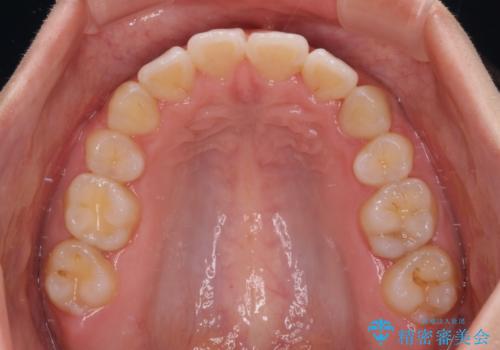

4本の歯を抜歯したことで、飛び出していた口元が引っ込み、横顔の印象が大きく改善されました。